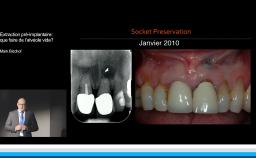

A partir de la description des facteurs de risque esthétique du bloc incisivo-canin maxillaire, de la présence d’os et de gencive autour des implants, le conférencier présente une succession de cas cliniques décrivant ses procédures chirurgicales et prothétiques.

• de déterminer le bon timing de chirurgie implantaire post extractionnelle

• de réfléchir sur la préservation à moyen-long terme de l’os autour des implants

• Ridge Preservation